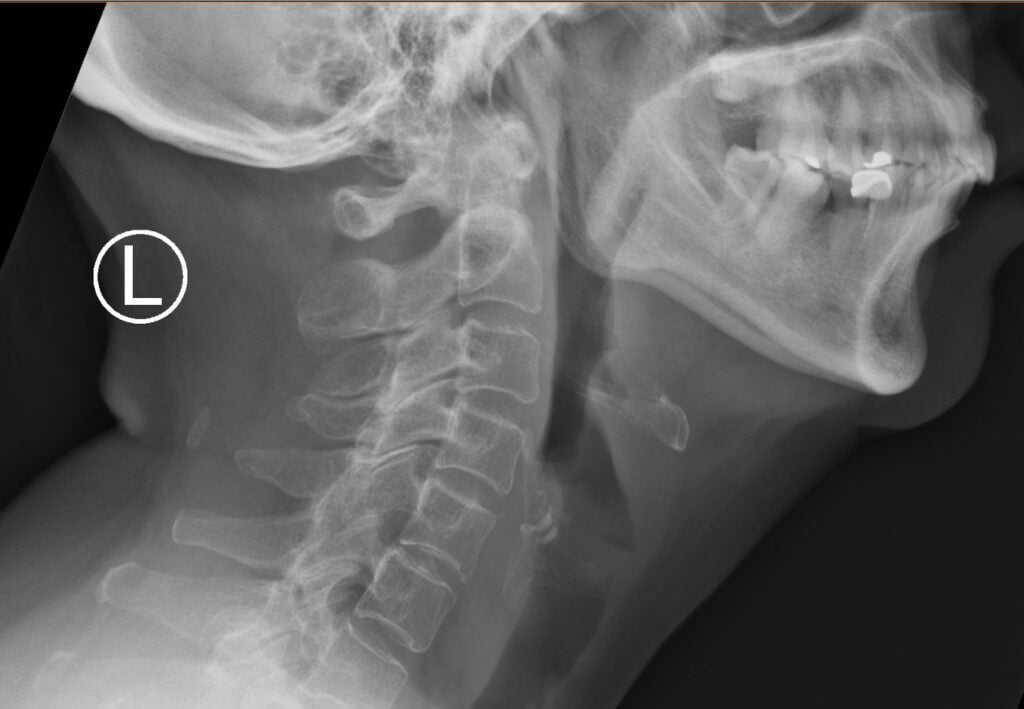

Neck CT swallowed fish bone perforated the hypopharanx into prevertebral space. radiologist What To Do If Child Swallowed Fish Bone Press into the stomach, also called the abdomen, with a quick, upward thrust — as if trying to lift the person up. Thousands of children swallow all kinds of objects every year. Fish bone stuck in the food pipe may be removed by passing a rigid scope (a long lighted tube) down the food pipe. Find out what to do. What To Do If Child Swallowed Fish Bone.

FISH BONE STRUCK IN NECK What To Do If Child Swallowed Fish Bone If you’re certain that your child has swallowed a small fish bone, you must first find out the exact location where it’s stuck. Find out what to do if you or someone you know accidentally swallows a fish bone and experiences discomfort or pain. If the bone didn't scratch your throat on the way down, you shouldn't have any further. What To Do If Child Swallowed Fish Bone.